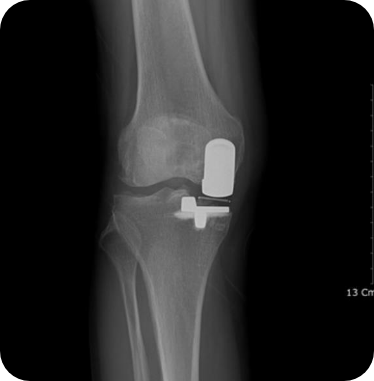

무릎인공관절 전치환술 사례1

• ▲ 수술 전

• ▲ 수술 후

무릎인공관절 전치환술 사례2